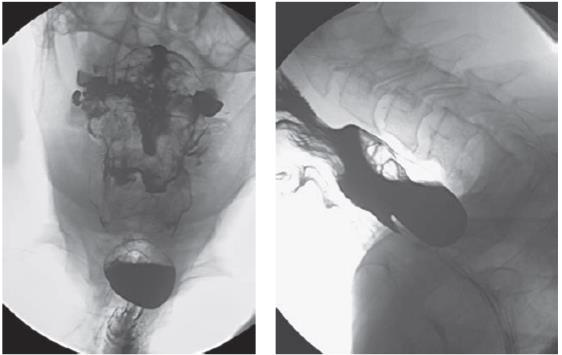

Homem, hígido previamente, queixa-se de disfagia e halitose há cerca de seis meses. Nesse período, apresentou três episódios de pneumonia. Realizou exame que gerou as seguintes imagens:

Fonte: JAMESON, Larry et al. Harrison’s Principles of Internal Medicine. 20. ed. New York: Mc Graw Hill Education, 2018

O tratamento adequado em relação à lesão é: